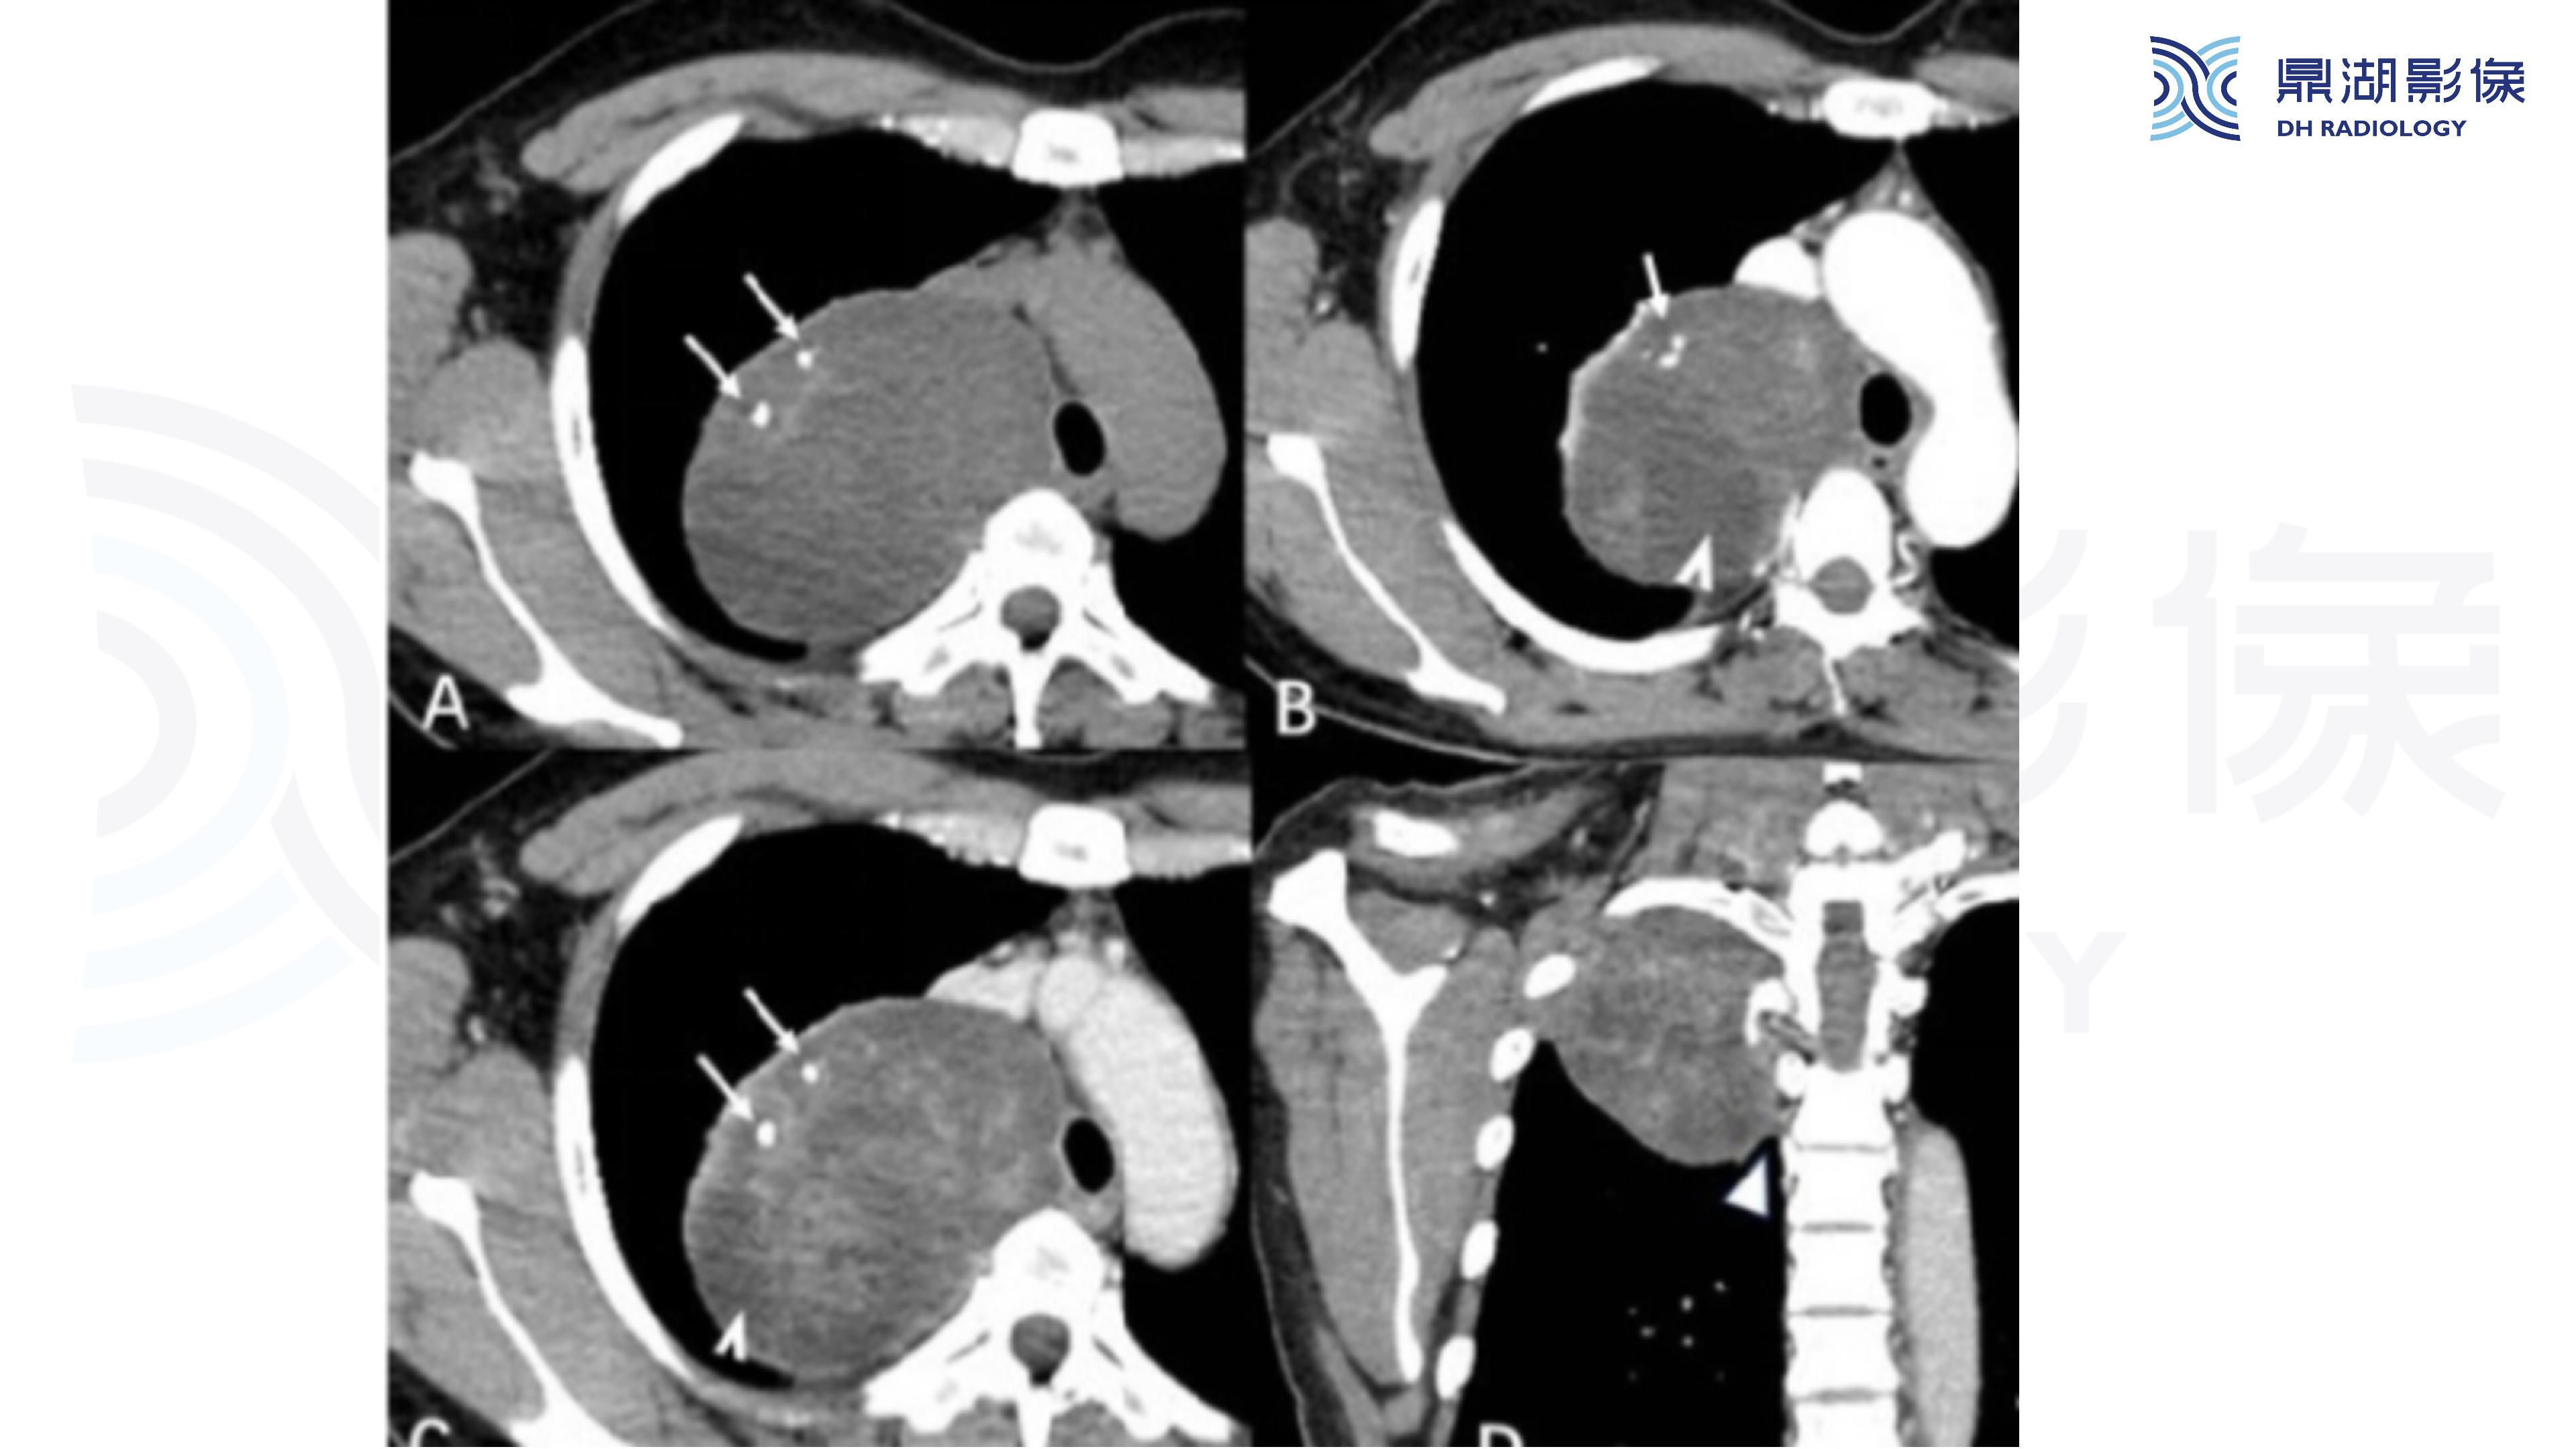

纵隔血管瘤-鼎湖社群读片病例